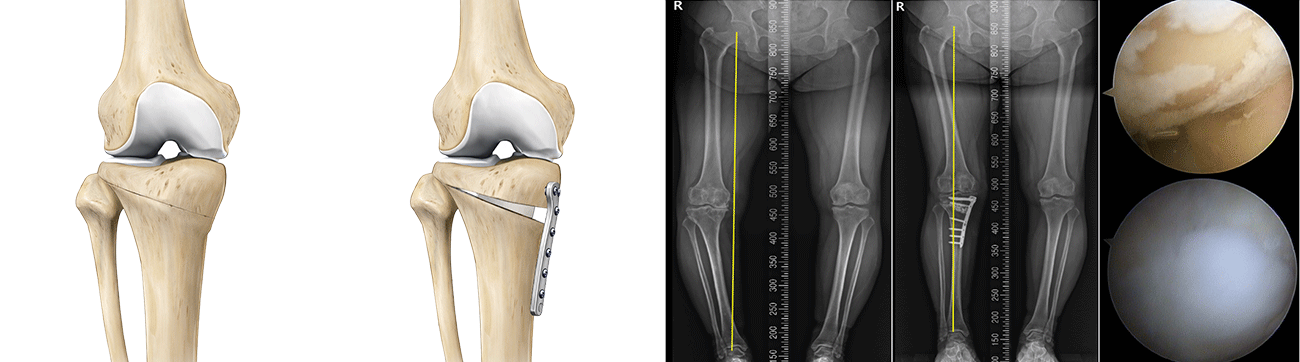

근위경골절골술은 오다리 변형으로 인해 무릎 안쪽 관절에 집중되는 체중 부하를 교정하기 위한 수술입니다.

무릎 아래 뼈인 경골의 정렬축을 조정하여, 이를 통해 무릎 안쪽 연골에 집중되던 부담을 줄이고 통증 완화를 기대할 수 있습니다.